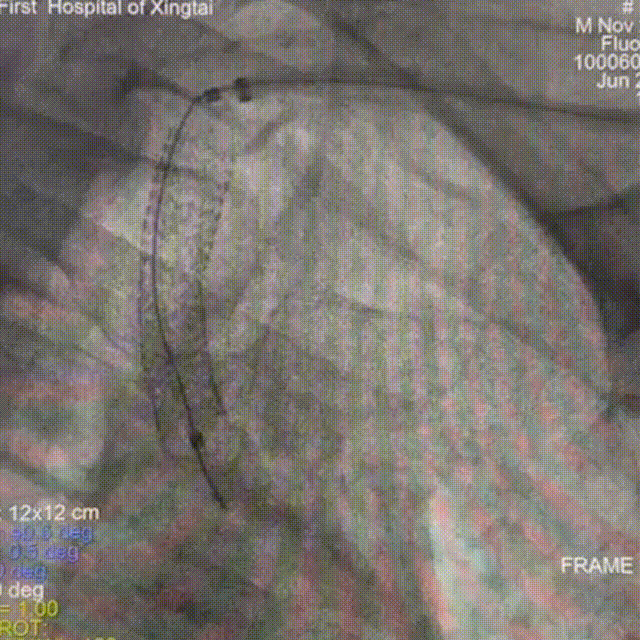

术前影像学检查结果

左侧锁骨下动脉重度狭窄。